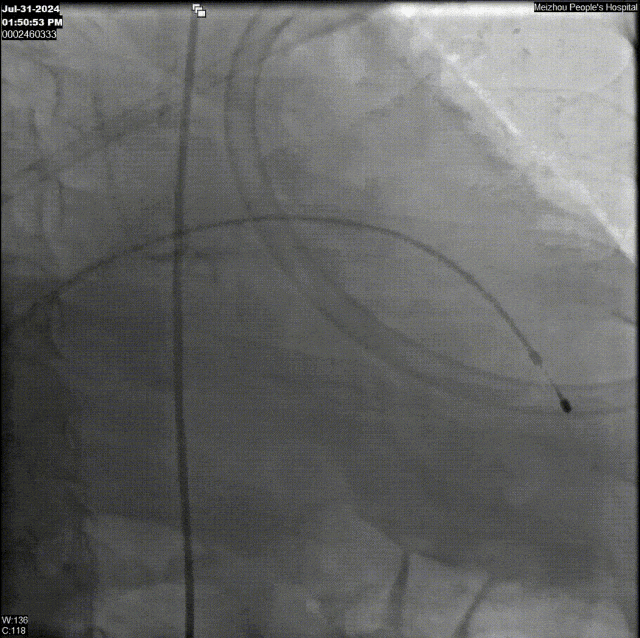

术中,手术团队精准操作器械缓缓进入患者体内,从右股动脉的主攻,到左股动脉与右肱动脉的巧妙辅助,形成了一套完美的“三路并进”策略,人工瓣膜在瓣环零位精准定位,辅助锚定器瞬间释放,确保了瓣膜的稳定植入与完美贴合。手术圆满完成,叠加封堵器械有效锚定人工主动脉瓣膜并成功释放,术后患者主动脉瓣反流明显改善。

术前主动脉根部造影:可见主动脉瓣大量反流,左心室扩大

最终造影观察:无PVL,冠脉正常显影,瓣膜最终位于瓣下约2mm